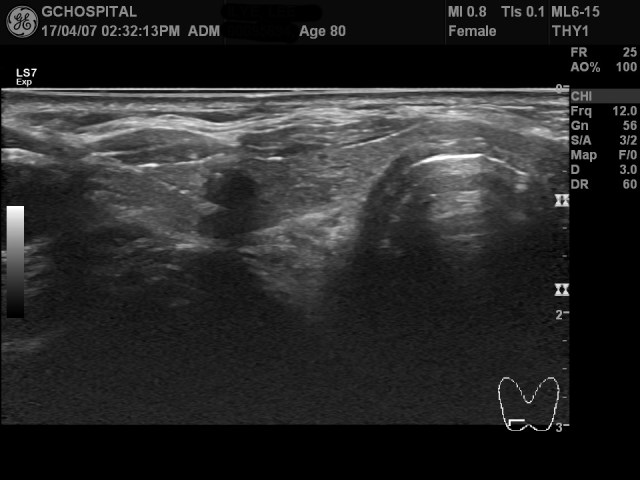

가장 안좋은 결과로 볼 수 있는(제가 검사를 못해서 결과가 안나온) insufficient specimen을 보면 위의 영상처럼 아예 dense calcification이었고, 검사 전부터 결과가 나올 가능성이 많지 않음을 예상해서 설명했음에도 불구하고 환자가 원해서 검사를 진행했었습니다.

그리고, 또 느끼는게 위의 영상처럼 무리한 흡입검사는 되도록 피하되, 검사에는 좀 더 자신감을 가져도 되겠다는 생각입니다. 정상적인 상황에서 검사가 잘 안되어서 insufficient specimen이 나오지는 않았으니까요.